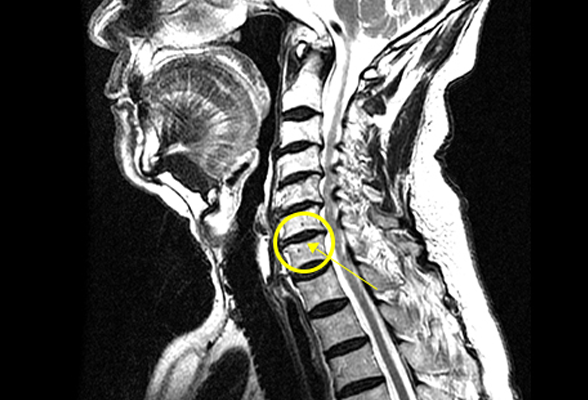

경추 척수증

경추의 퇴행성 질환 때문에 발생한 압력이 척수(Spinal cord)를 누르면서 이차적인 원인에 의해 발생한 척수 기능장애 입니다.

경추 추간판의 중앙 탈출이 심한 환자나 경추증과 같은 기존의 신경관 협착이 있는 환자가 가벼운 외상을 입었을 때 발병됩니다.

비수술 치료 : 약물치료, 물리치료, 신경차단주사, 경막 외 신경성형술

수술치료 : 경추체 전방 고정술, 경추체 추궁 절제술